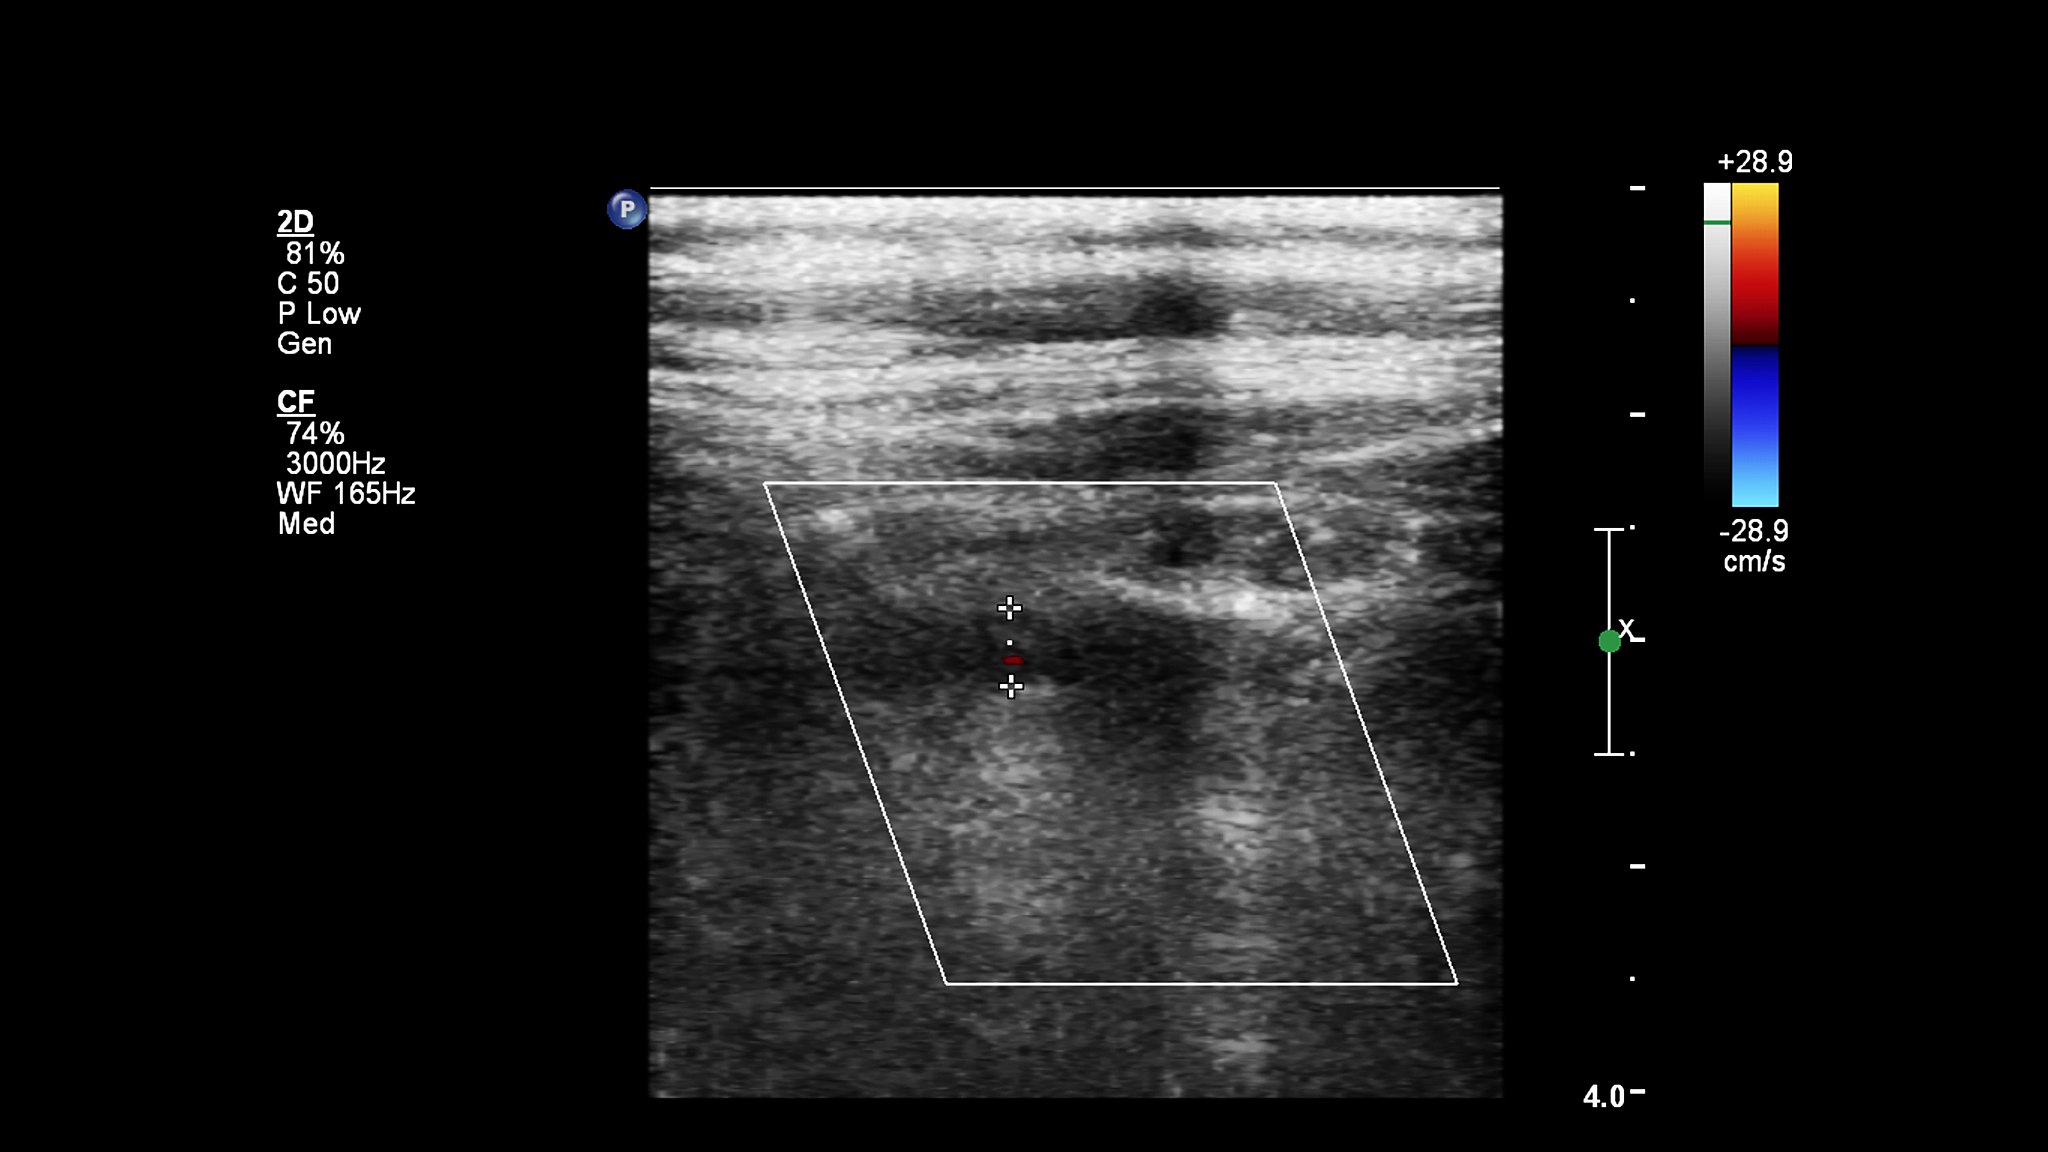

超声三级手术权限包括:超声引导下的穿刺、活检、截瘤、消融、引流等手术操作。

超声四级手术权限相比三级手术权限更高,包括:超声引导下的介入治疗、手术操作,如血管栓塞、介入治疗肿瘤、心脏介入治疗等。

超声四级手术权限要求医生具备更高的技术水平和更丰富的临床经验。同时,医生需要通过相关考试获得资格认证才能获得超声四级手术权限。